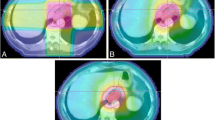

NTCP model

Lyman NTCP model parameters and corresponding 95 % confidence intervals for human GI toxicity data are summarized in Table 3. Because dose volume histograms were not available, we estimated parameters assuming 1 to 5 % of the duodenum received the study’s prescribed dose. If multiple doses or fractionation schemes were employed in a single study, the median study dose was used for our analysis. In some instances, the median study dose was not provided and could not be calculated because the exact dose distribution was not reported. In these limited cases, the mean dose as reported by the authors was used. According to published reports, an α/β ratio of 3.0 or 4.0 is appropriate for bowel toxicity, thus we estimated the median or mean EQD 1.84 using a α/β ratio of 3 or 4 (Table 3) [25, 26]. Figure 1 shows overall GI toxicity rate as a function of median or mean dose for each study and the maximum likelihood fit of the LKB model for α/β ratio of 3 and 4 and duodenal volume 1 % and 100 % (Fig. 1).

We also examined the relationship between radiation dose and late gastrointestinal complications. We specifically examined studies that used hypofractionated treatment irrespective of modality (between 1 and 5 fractions). Several patients also received conventionally fractionated radiotherapy. We calculated the EQD 1.84 for all radiation treatments given to the volume, and summed them arithmetically. Whether the linear-quadratic model accurately represents the true biologic efficacy of hypofractionated radiation treatments is an issue of debate, especially when the fraction size is large [27]. In our analysis, we noticed a clear relationship between dose and toxicity (Fig. 1). Univariate analysis of multiple study characteristics identified dose as a significant predictor of toxicity (Table 4). A similar literature analysis attempting to identify a therapeutic window for SBRT use in pancreatic adenocarcinoma by Brunner and colleagues also identified a significant relationship between dose and gastrointestinal toxicity [28]. The authors compiled gastrointestinal toxicity from 16 literature reports following SBRT of the pancreas. Linear regression showed a positive correlation between grade ≥ 3 toxicity and study EQD3 2 (R2 = .77). A 5 % rate of grade ≥ 3 toxicity was associated with an EQD 23 of 80 Gy. Interestingly, examining the raw data for Fig. 1 based on a similar EQD 1.83 , the 5 % complication rate is reached at 80 Gy, and with an EQD 1.84 the 5 % complication rate is reached at 75 Gy. Therefore, both studies seem consistent in this respect.

Because dose volume histograms were not available, we estimated NTCP model parameters assuming duodenal volumes of 1–5 % received the prescription dose, which is consistent with clinical practice and as reported in some of the series we examined. For example, Chang and colleagues as well as Schellenberg and colleagues treated patients with 25 Gy in a single fraction using SBRT. In both studies, the volume of duodenum receiving more than 22.5 Gy was less than 5 % [10, 13]. Willett and colleagues as well as Goldson and colleagues retracted normal GI structures away from the cylinder applicator when treating patients with IORT [18]. Nishimura and colleagues similarly retracted normal GI structures outside the treatment field. In cases where the GI structures could not be completely excluded, a smaller dose was applied to the entire field and a higher dose applied to the central region targeting the tumor (field-in-field). Thus, an upper limit of 5 % of duodenal volume exposed to the maximum dose seems reasonable.